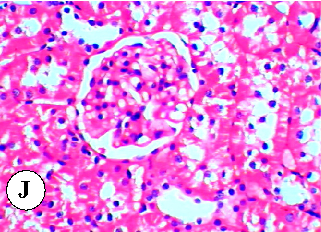

Figure 23

Figure 23 Chart

Final summary data from the hepatorenal toxicity study, consolidating the evidence for plant oil protection against diazinon-induced organ damage in rats.

Protective effect of some plant oils on diazinon induced hepatorenal toxicity in …